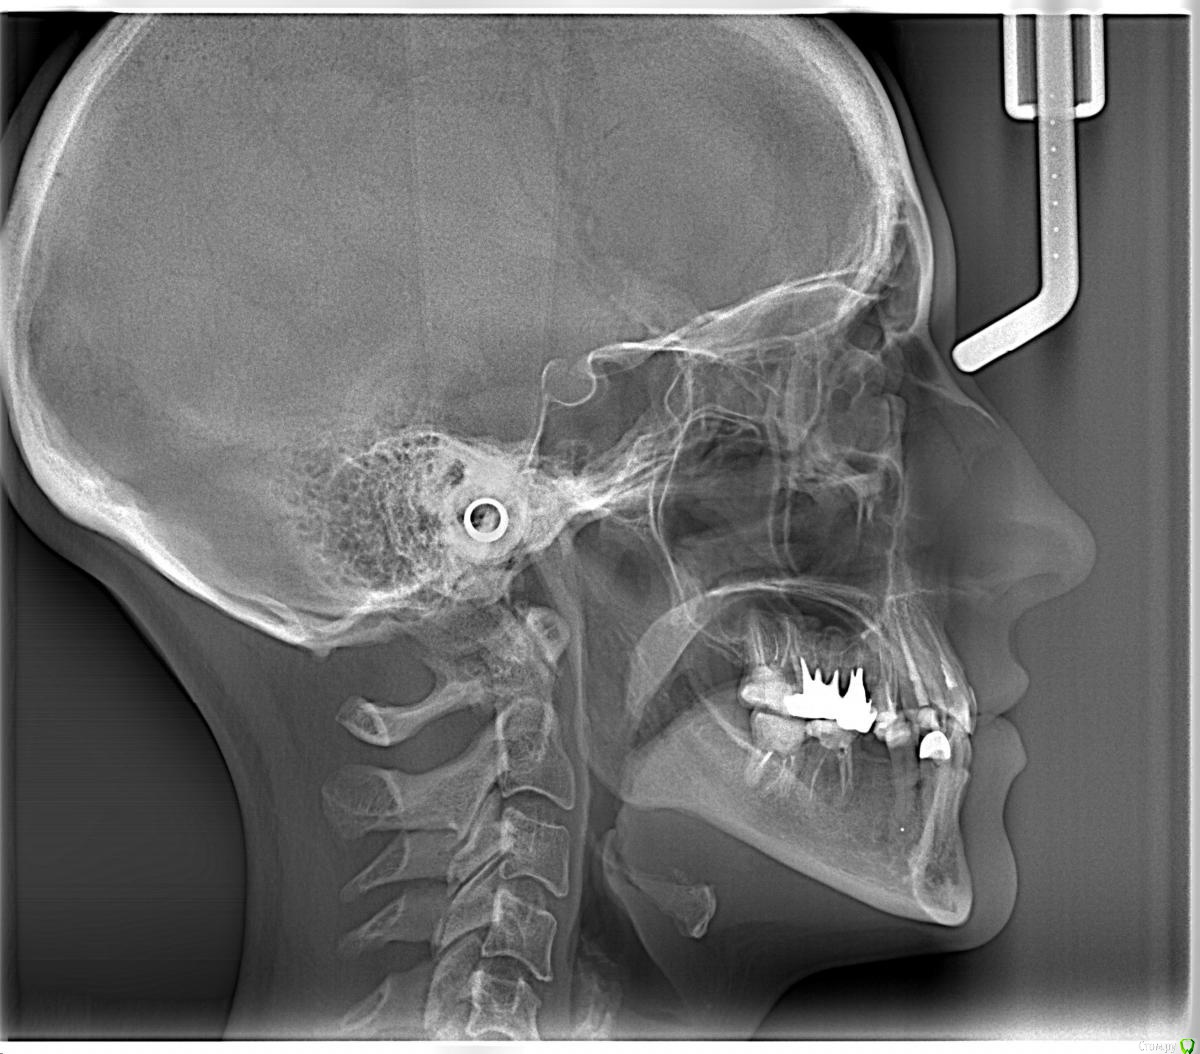

Здравствуйте, Коллеги! Хочу спросить совета по такому случаю. Пациентка 33 года. В детстве удалили 12 зуб, пространство закрыли на съемном аппарате. В подростковом возрасте удалили все остальные отсутствующие зубы. Сейчас носит бюгель. Вопрос такой: заниматься ли мне, как ортодонту формированием полноценного межчелюстного соотношения, или просто решить локальные проблемы и отдать на функциональную реабилитацию ортопеду? И если все-таки заниматься мне, то как??? Лечение такого третьего класса - элементарно для многопетлевой при наличии адекватной опоры, но вот такая адентия заставляет меня сомневаться. Заранее спасибо за ответы!

это секретный 3й или вынужденное положение?

Прошу прощения, трг не увидела с телефона..